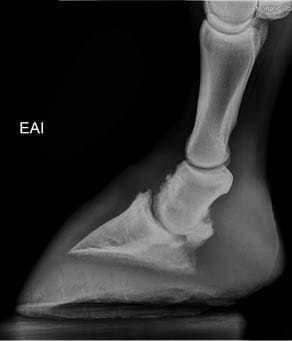

- Infosura o laminitis

- Cuidados del casco y herrajes ortopédicos

La radiología digital directa es una herramienta indispensable para el estudio v valoración en numerosas áreas de la atención veterinaria: valoración de cojeras, exámenes pre-compra, estudios radiológicos, diagnósticos más precisos en patologías, heridas, enfermedad…

- Medidas e imagen 3D para evaluación del pie equino

- Imagen hibrida. Diagnóstico v herrado